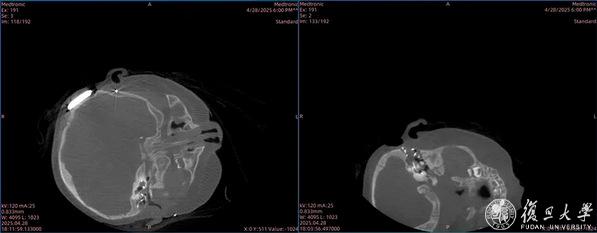

“再等下去,孩子的言语和认知发育都会受到不可逆影响。”多轮讨论后,陈文霞团队为小宇制定了“双耳差异化植入方案”,还请来了“透视眼”O臂机(术中辅助CT技术)术中精准导航。

专家团队根据术中影像为患儿采取个性化植入方案

手术台上,主刀医生像完成精密工作的“管道工”,在小宇左侧采用耳后微创入路,保留重要骨性结构,用自体肌瓣充当“防水补丁”堵住风险区,防范脑脊液漏并成功植入电极,诱发出神经反应;右侧则创新采用水平半规管“借道”,以非标准角度精准植入电极。3个多小时里,O臂机如同“实时地图”,让每一步操作都清晰可见,为这例高难度人工耳蜗植入手术保驾护航。

术中“O”臂机成像后判断双耳耳蜗电极位置符合预期